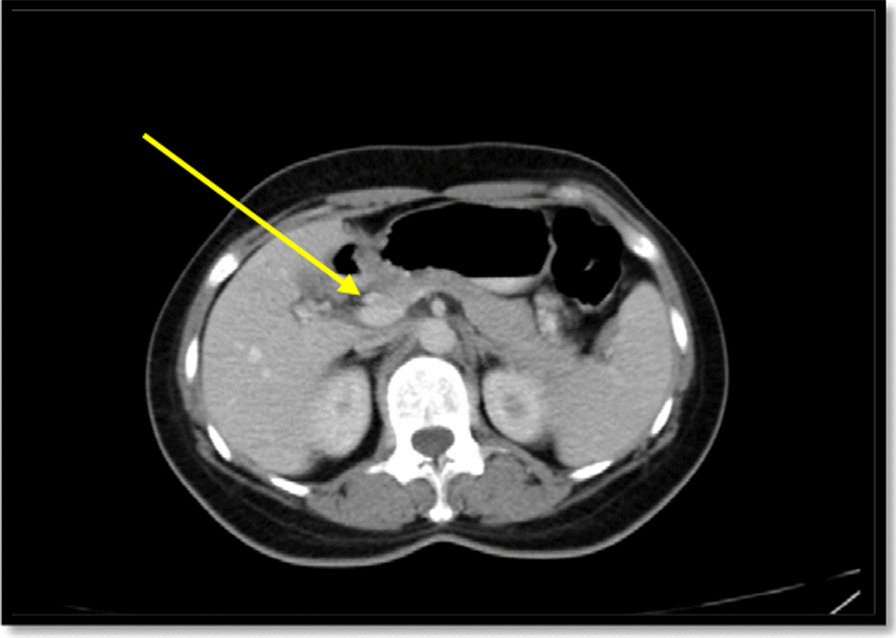

In spiral chest CT scan with and without intravenous (IV) contrast, obtained axial images, represented a 29 × 18 mm soft tissue fullness at middle to distal esophagus (at the level of the carina to the level of the main pulmonary artery), which was suggestive for a tumoral lesion. No lung metastasis was found. In spiral abdomen and pelvic CT scan with oral and IV contrast, there was a 12 × 9 mm LN within gastrohepatic ligament (Fig. 2). In the abdomen and pelvic sonography, there was a 10 × 9 mm hypoechoic lesion between the left liver lobe and greater curvature which was suggestive of lymphadenopathy (LAP) (Fig. 3.).

Fig. 3.

Spiral abdomen and pelvic CT scan: a lymph node within gastrohepatic ligament shown with a yellow arrow